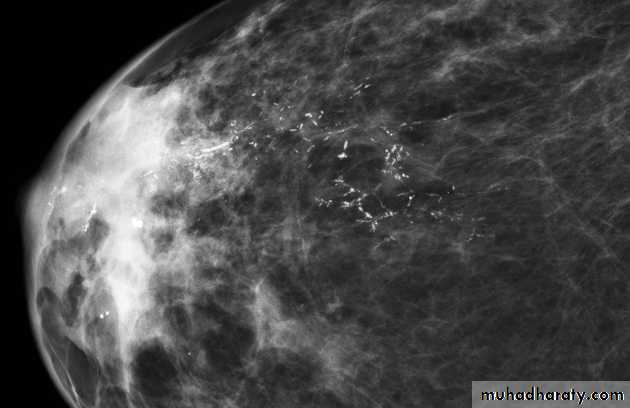

Micro calcifications

Micro calcifications are tiny specks of calcium in the breast. Micro calcifications seen on a mammogram are of more concern than macrocalcifications, but they do not always mean that cancer is present. The shape and layout of microcalcifications help the radiologist judge how likely it is that cancer is present.

In most cases, the presence of microcalcifications does not mean a biopsy is needed. But if the microcalcifications have a suspicious look and pattern, a biopsy will be recommended. (During a biopsy, the doctor removes a small piece of the suspicious area to be looked at under a microscope. A biopsy is the only way to tell if cancer is really present.)

A mass it is calcification & margin

>>>>>> A mass will detected>>>>>> if it is with or without calcifications, change seen on a mammogram.

>>>>>> it is Margin